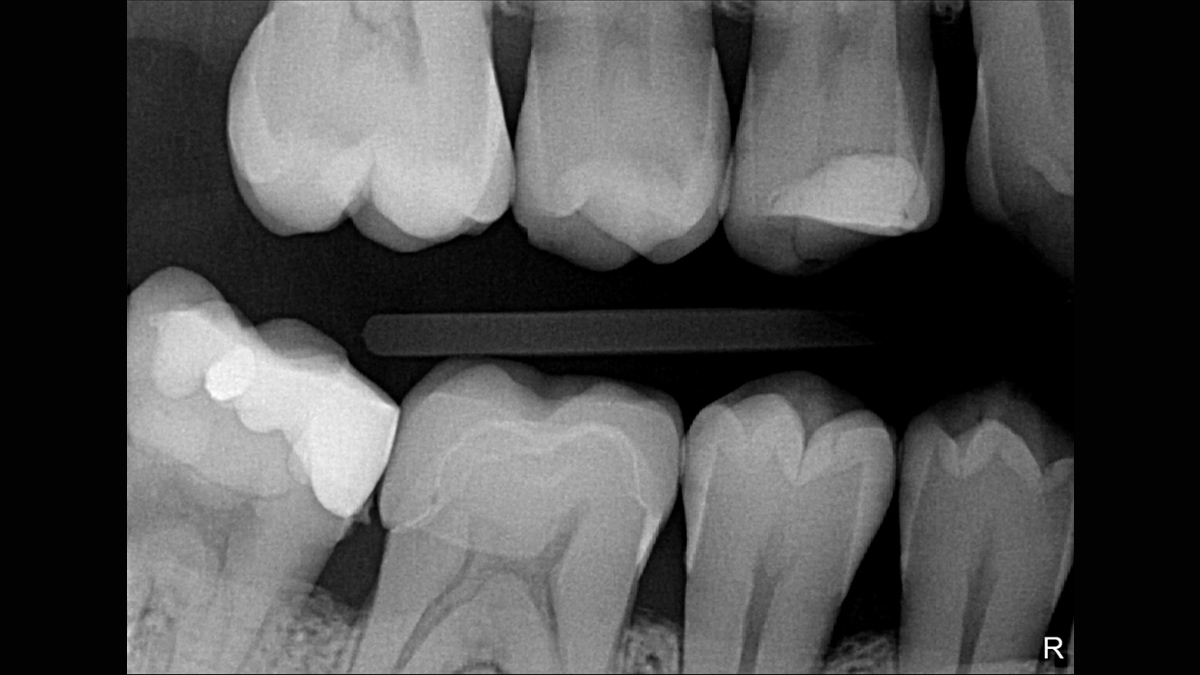

Excellent Images for Optimal Patient Care

Excellent image quality is just the beginning with the Xios XG Supreme intraoral sensor. With a number of enhancement options and the ability to easily adjust your images to support your individual preferences, you get more than just a sensor; you get an intraoral solution. Equipped with multiple sensor sizes, cable lengths, and connectivity options, you truly have a tool that adjusts to you, not the other way around.